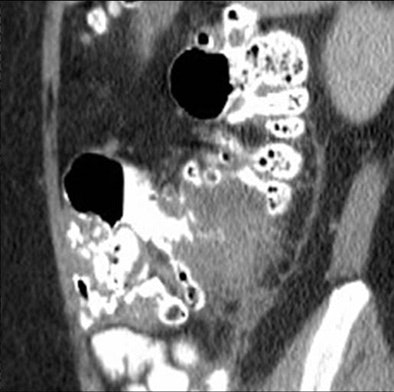

![]() |

| Above, appendicitis diagnosed with both oral and IV contrast. Below, another patient with appendicitis diagnosed with IV contrast alone, both with surgical confirmation. |

Surgical confirmation was available for the appendicitis cases. "In the oral and IV group, 14 patients had surgically proven appendicitis; sensitivity and specificity for the CT scans being 100% and 98.5%, respectively," Anderson said. "For the IV-only group, 13 patients had surgical proof of appendicitis; sensitivity and specificity being 100% and 98.5%, respectively, as well."